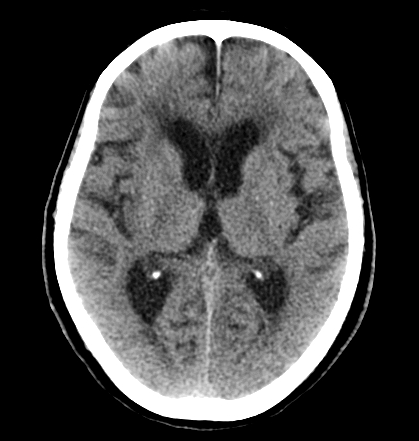

Компьютерная томография при герпетическом энцефалите хорошо выявляет следующие анатомические признаки:

В нативном режиме определяется участок пониженной плотности в медиобазальных отделах височной доли, в ряде случаев с нарушением симметрии структур и сдавлением боковых желудочков.

В режиме сканирования мягких тканей визуализируется локальный отёк височной и лобной долей с потерей различимости коры и белого вещества.

При тяжёлой форме может быть определена зона паренхиматозного некроза и геморрагического пропитывания ткани.

- Объём и локализация воспалительных изменений в височной доле определяются по сниженной плотности с достаточной чувствительностью на поздних стадиях.

- Признаки внутричерепного давления, включая сдавление желудочков и срединный сдвиг, фиксируются в экстренной ситуации.

- Наличие геморрагического компонента и зоны некроза оценивается по плотности ткани при подозрении на тяжёлое течение.

- Состояние борозд, цистерн и базальных структур позволяет определить выраженность отёка мозга.